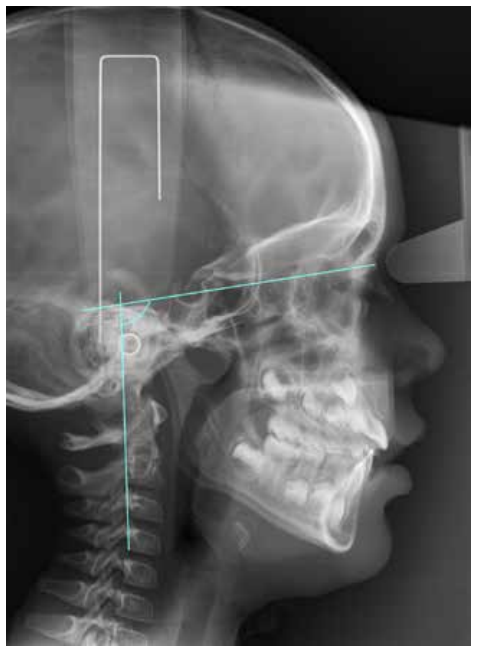

Another variable studied was the CVT-SN, which is the angle formed between SN and the line that runs through the postero-superior and postero-inferior points of the four cervical vertebrae (Figure 2).